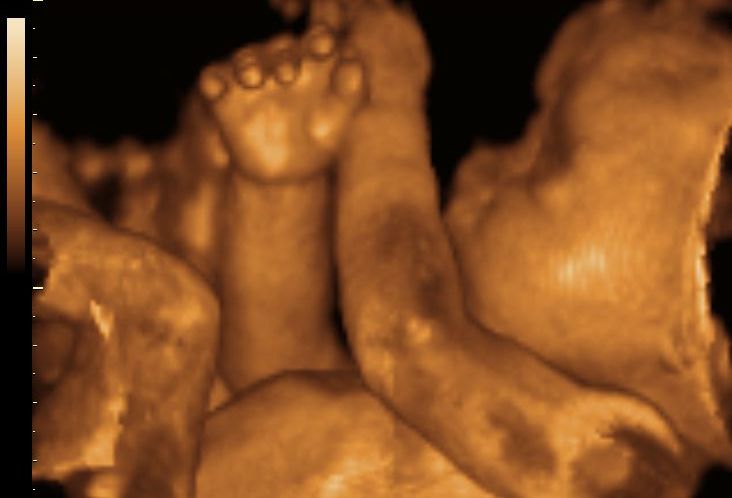

Bu ultrason ile bebeğin yüz hatları, burun, dudak yapısı, eller, ayaklar, mimikler ve hareketleri net şekilde izlenebilir.

Bebek esniyorsa, parmağını emiyorsa ya da gülümsüyorsa bunlar anlık olarak izlenebilir.